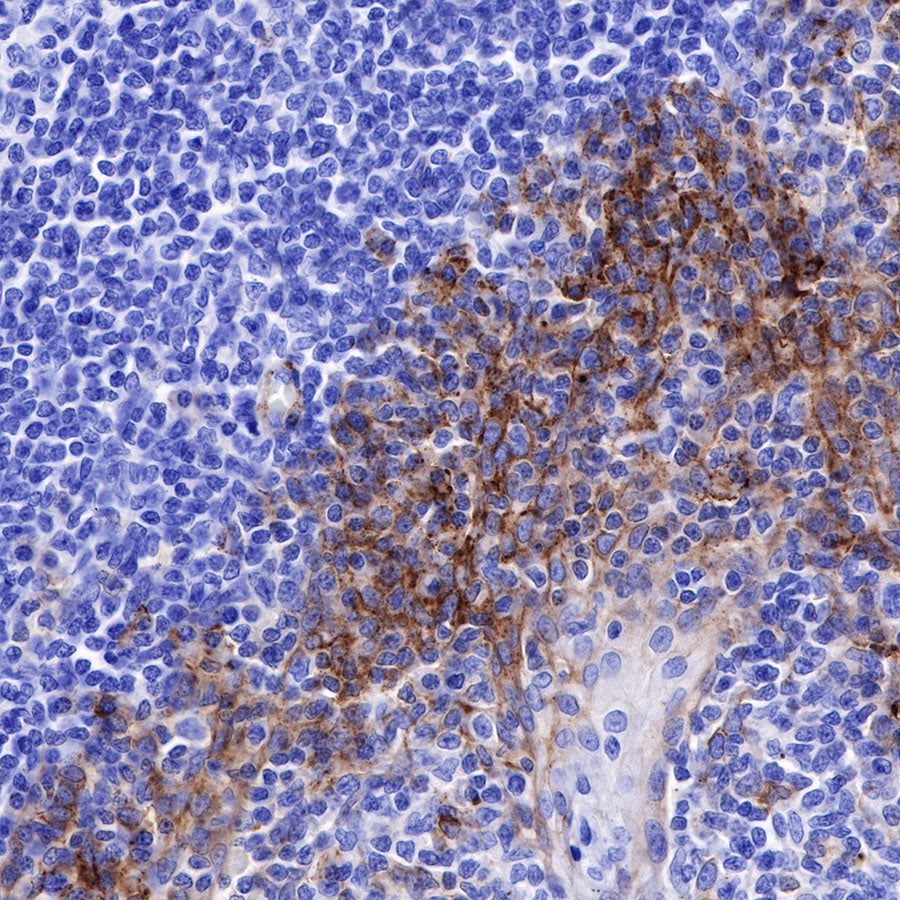

Syndecan-1 (CD138) is mostly restricted to epithelia, and bears heparan sulfate chains that are capable of interacting with a large array of polypeptides, including extracellular matrix components and potent mediators of proliferation, adhesion and migration. For this reason, it has been studied extensively with respect to carcinomas and tumor progression. Frequently, but not always, syndecan-1 levels decrease as tumor grade, stage and invasiveness and dedifferentiation increase. However, in some tumors, levels of syndecan-1 increase, but the characterization of its distribution is relevant. There can be loss of membrane staining, but acquisition of cytoplasmic and/or nuclear staining that is abnormal. Moreover, the appearance of syndecan-1 in the tumor stroma, either associated with its cellular component or the collagenous matrix, is nearly always a sign of poor prognosis [PMID: 33921767].

Picture

Immunohistochemistry